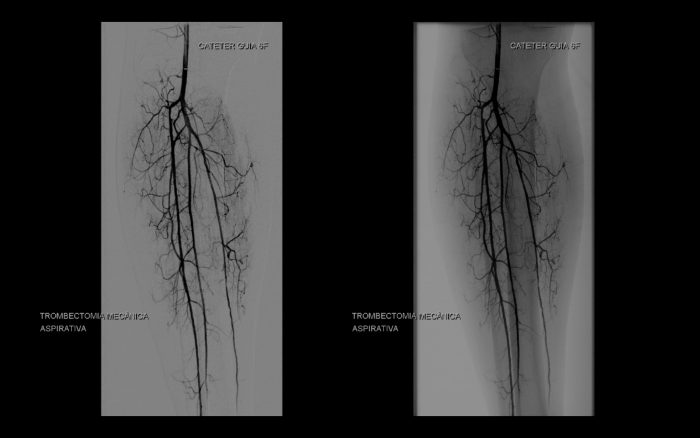

O JETSTREAM é um dispositivo de aterectomia rotacional e aspirativa, desenvolvido pela Boston Scientific, permite recanalizar obstruções arteriais através da redução da carga de placa aterosclerótica, mesmo calcificada ou trombótica, e da hiperplasia miointimal com baixa taxa de embolia distal (1,6%), diminuindo as limitações e complicações da angioplastia tradicional, como dissecção e recolhimento elástico precoce, e sem os efeitos dos elementos sintéticos deixados no vaso como os Stents.

Esse dispositivo de aterectomia pode ser utilizado também em estenoses ou oclusões intra-stent apresentando taxa de recanalização de 91% e sem causar deformidades ou fraturas do stent.